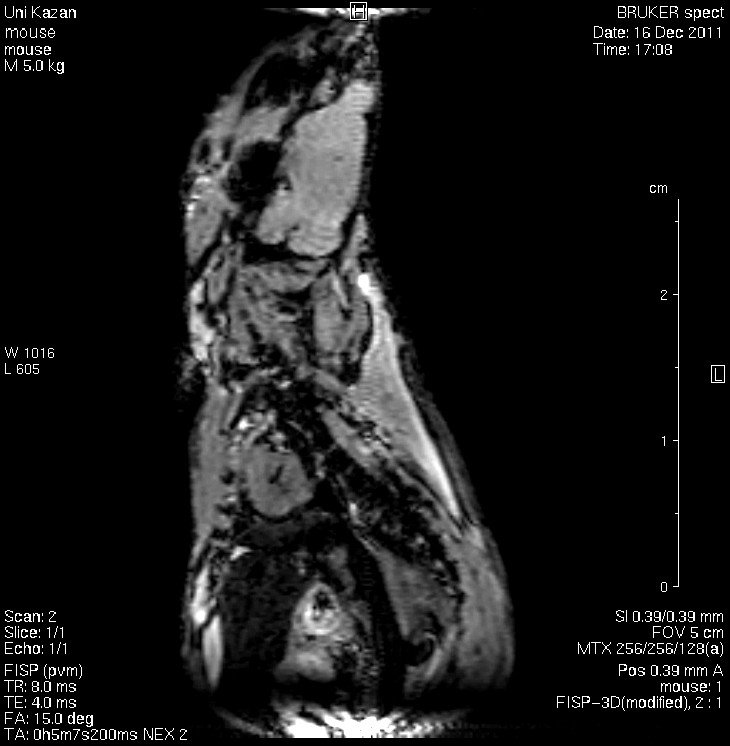

Кафедра физики молекулярных систем - это коллектив профессионалов, специализирующихся на исследованиях структуры и динамики сложных молекулярных и биомолекулярных систем методами ядерного магнитного резонанса (ЯМР). При этом используются самые передовые методики ядерного магнитного резонанса, в том числе методы градиентного ЯМР и магнитно-резонансной томографии, а также теоретические исследования с помощью современных численных методов и компьютерного моделирования.